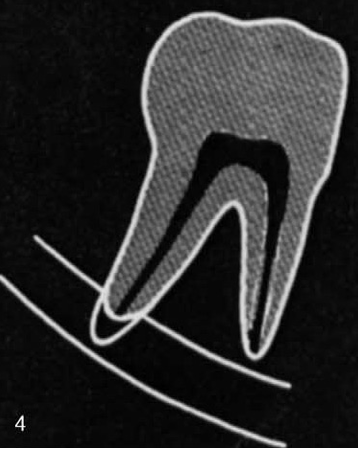

what is this?

Deflection of root